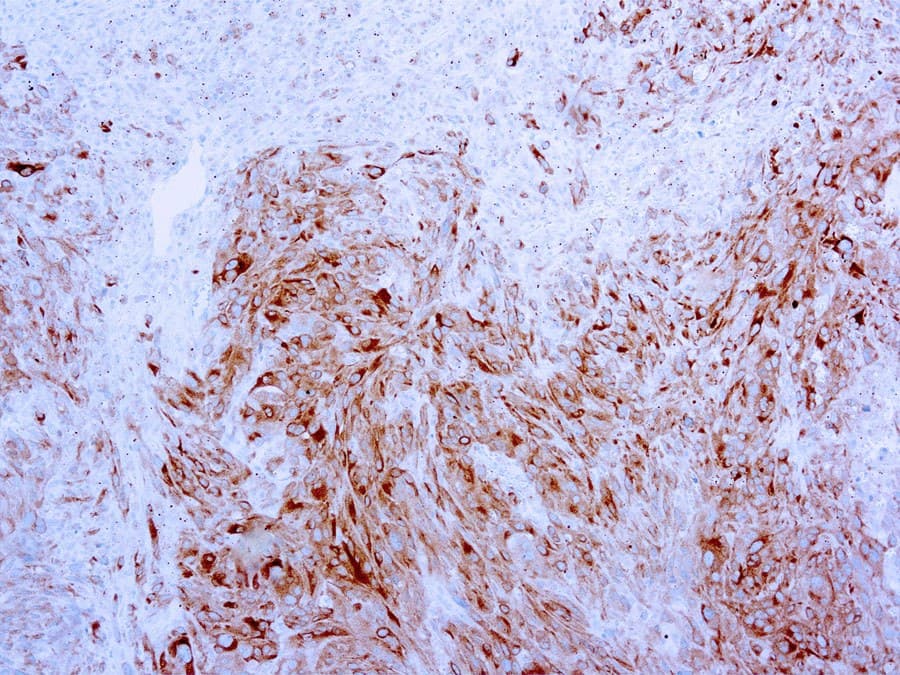

MART-1, noto anche come Melan A o Melanoma Antigen Recognized by T Cells 1, è un antigene proteico che si trova specificamente sui melanociti della pelle normale, della retina e dei nevi, e non in altri tessuti normali. È una proteina di membrana di tipo III con un peso molecolare di 22-24 kDa. È presente nel reticolo endoplasmatico (ER) e nella rete trans-Golgi (TGN). MART-1 è una proteina del lineage dei melanociti.

MART-1 etichetta sia i melanociti normali che le cellule malate con differenziazione melanocitaria. È utile per la diagnosi dei tumori con differenziazione melanocitaria, in particolare del melanoma metastatico. L'identificazione di MART-1 apre inoltre la possibilità di sviluppare immunoterapie per i pazienti affetti da melanoma. L'anti-MART-1 (Melan A) è quindi utile come marcatore dei tumori melanocitari e come ausilio nella diagnosi dei melanomi metastatici.